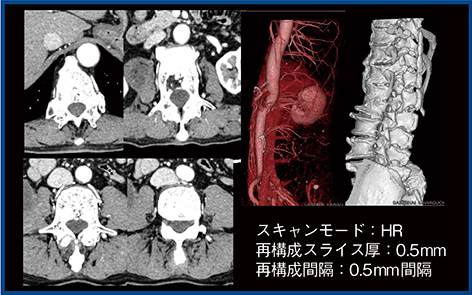

2.腹部血管

超高精細CTではAiCEを適用することでノイズを抑えつつ,椎体と動脈の間隙を鮮明に確認できる(図8)。また,骨除去も既存CTでは非剛体サブトラクションを用いていたが,超高精細CTではワンクリックで行えることから,超高精細CTによるポストプロセスの変化を実感している。

図8 椎体の動脈描出能の比較